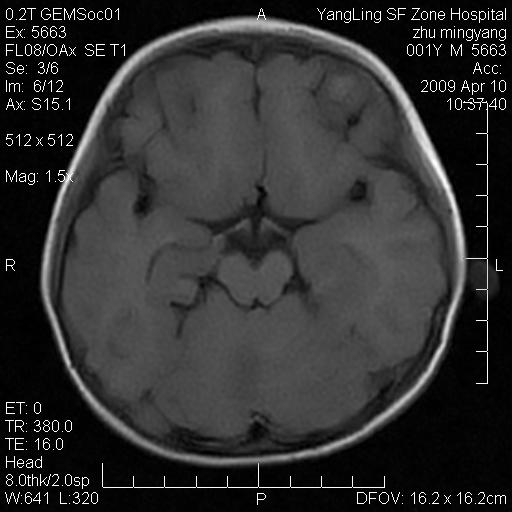

患者:1岁半,两天前外伤收住我院,ct检查小脑占位

考虑星形细胞瘤,建议增强

髓母细胞瘤或血管母细胞瘤,增强后可以鉴别;影像资料见 <。鱼博浪老师的《中枢神经系统ct与mr鉴别诊断》 小脑部肿瘤章节。

髓母细胞瘤或血管母细胞瘤!支持!

支持考虑髓母细胞瘤

考虑----髓母细胞瘤可能性大

考虑髓母细胞瘤或室管膜瘤。

支持髓母细胞瘤。

考虑髓母细胞瘤。

考虑髓母细胞瘤或星形细胞瘤

考虑髓母细胞瘤.

小脑肿瘤.考虑髓母细胞瘤可能.

就病灶部位及临床资料首先考虑髓母.